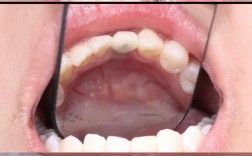

即刻种植指拔牙后立即在新鲜拔牙窝内植入种植体,减少手术次数;即刻负重则是在种植体植入后,同期安装临时牙冠,实现“即种即用”。

- 微创结合:这两种技术常与数字化导板联合,利用微创切口植入种植体,减少手术创伤,前牙区拔牙后,若牙槽骨条件允许,通过即刻种植可避免拔牙后3-6个月的等待,且微创操作能最大限度保留牙龈形态,美观效果更佳。